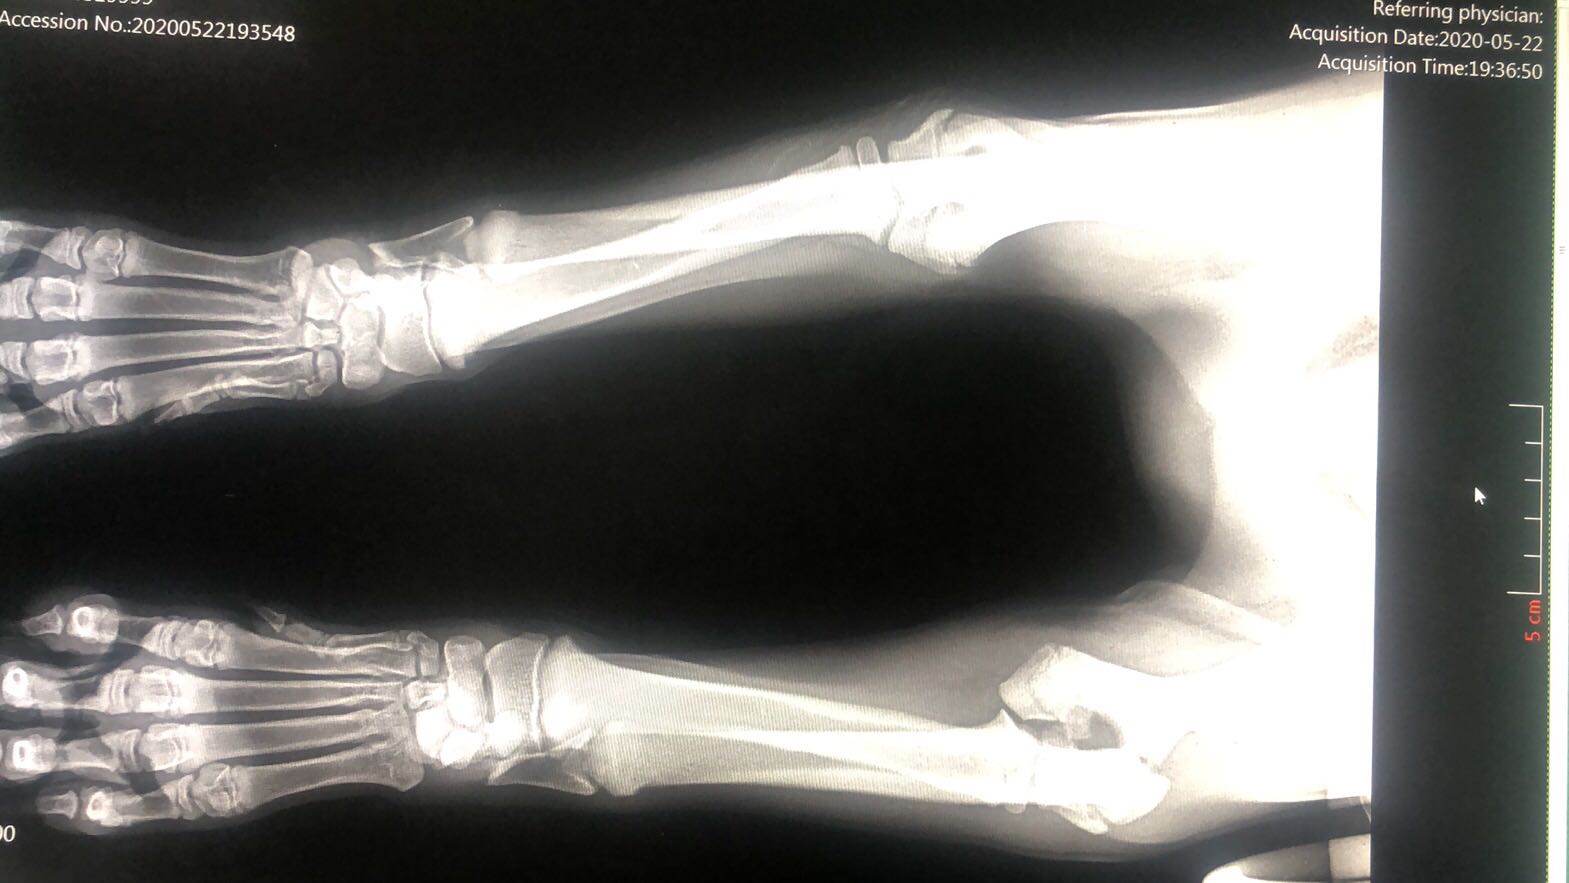

宠物土豆从移动的电动车上掉下来,出现左前肢跛行,腕关节弯曲不敢着地,关节肿大。经X光片显示,关节肘头与冠状骨斜骨折。经两个小时手术,将断骨联结,手术***成功。

上一条:关节肘头与冠状骨斜骨折。经两个小时手术,将断骨联结